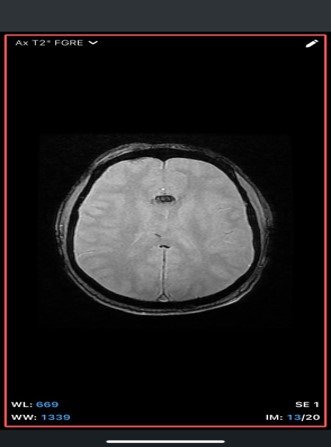

An extra-axial TI/T/Flair hyperintense lesion in midline at the inferior edge of the interhemispherie fissure extending along the superior margins of the corpus callosum with areas of blooming consistent with calcification and no post contrast enhancement –likely pericallosal lipoma.

• Well-defined, homogeneous, hypodense lesion (-50 to -100 HU, consistent with fat).

• May show peripheral or central calcifications (~50% cases).

• No enhancement with contrast.

• MRI

• T1-weighted: Hyperintense (fat signal).

• T2-weighted: Variable, usually hyperintense; may show chemical shift artifacts.

• Fat-suppressed sequences: Complete signal suppression confirms fat composition.

• Post-contrast: No enhancement.